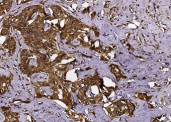

Product information "Anti-CHI3L2/YKL-39 Monoclonal Recombinant Antibody"

Chondrocyte protein 39 (YKL-39), also known as Chitinase 3-like 2 (CHI3L2), is a secretory protein of articular chondrocytes belonging to the glycosyl hydrolase 18 family. Its highest expression is in chondrocytes, followed by synoviocytes, lung and heart. YKL-39/CHI3L2 is not detected in spleen, pancreas, and liver. YKL-39/CHI3L2 may also be expressed in developing brain and placenta. YKL-39/CHI3L2, a cartilage-related protein, is found to induce arthritis accompanied by pathologic changes in bone and cartilage. A better understanding of the immune response against cartilage-related components including YKL-39 may help to elucidate the pathological processes of arthritic disorders. Upregulation of YKL-39/CHI3L2 in osteoarthritic cartilage suggests that YKL-39/CHI3L2 may be a more accurate marker of chondrocyte activation than YKL-40, although it has yet to be established as a suitable marker in synovial fluid and serum. The decreased expression of YKL-40 by osteoarthritic chondrocytes is surprising as increased levels have been reported in rheumatoid and osteoarthritic synovial fluid, where it may derive from activated synovial cells or osteophytic tissue or by increased matrix destruction in the osteoarthritic joint. YKL-39 and YKL-40 are potentially interesting marker molecules for arthritic joint disease because they are abundantly expressed by both normal and osteoarthritic chondrocytes. Protein function: Lectin that binds chitooligosaccharides and other glycans with high affinity, but not heparin. Has no chitinase activity. [The UniProt Consortium]

| Application: | IHC (paraffin) |